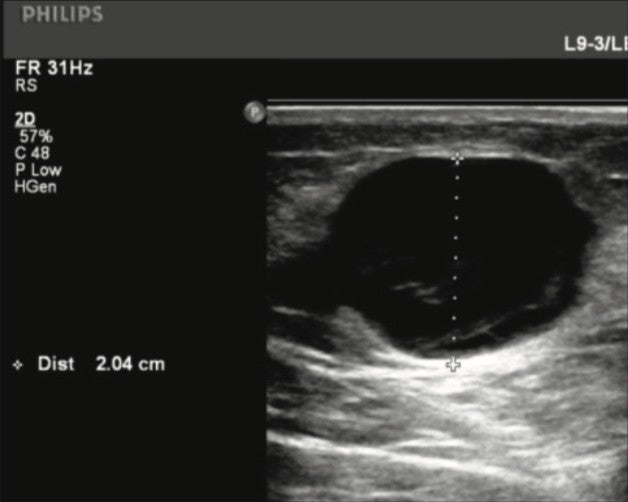

Figure 1. Thigh GSV Tributary pre-Varithena treatment.

The left Great Saphenous Vein (GSV) had a large refluxing branch from the groin level which measured 23.2mm at the groin and 20.4mm at the mid-distal thigh where it rejoined the GSV.

Reflux was 3.2 seconds at the groin and 4.7 seconds at the proximal-mid thigh.